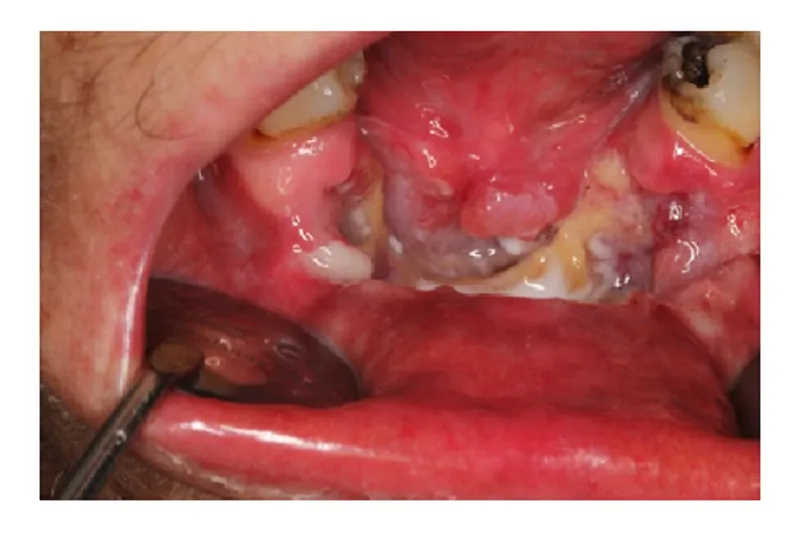

BAGGRUND – Planocellulært karcinom udgået fra mundhulens overfladeepitel er den hyppigste (> 90 %) form for oral cancer. De kliniske tegn på planocellulært karcinom er typisk et ikke-helende sår med voldformede rande og induration. Der kan dog også forekomme røde og hvide samt nodulære forandringer uden ulceration.

PATIENTTILFÆLDE – En 55-årig kvinde blev henvist til Kæbekirurgisk afdeling, Sydvestjysk Sygehus Esbjerg, med henblik på diagnostik og behandling af en nekrotisk knogledefekt i underkæben efter i en periode at være blevet behandlet kirurgisk i privat praksis. Klinisk sås en stor ulceration med voldformede rande og stor destruktion af processus alveolaris. CBCT viste stor destruktion af den faciale knogle i underkæbefronten. Patienten blev henvist til Øre-næse-hals-afdelingen pga. mistanke om planocellulært karcinom. Patienten kom herefter i kræftpakkeforløb, hvor diagnosen blev bekræftet ved biopsi. En primær resektion blev fulgt op af stråle- og kemoterapi. Fem måneder postoperativt blev der konstateret recidiv ekstraoralt på hagen, som blev behandlet med palliativ kemoterapi.